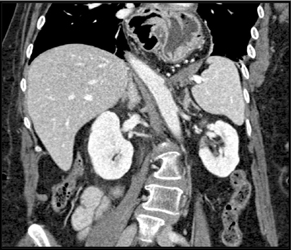

Antral Carcinoma